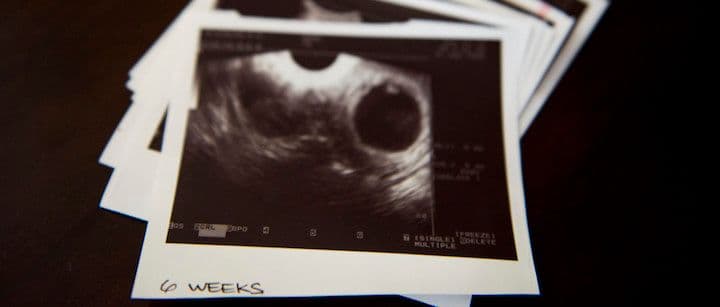

Your body goes through many changes throughout the first trimester, as does your baby. Even in the first few weeks after conception, the fetus begins growing at a rapid pace, magically transforming from a beating heart and formed organs to developing arms, legs, and facial features. Here are some things that will happen as your baby goes through the first 12 weeks of life.

Your baby will go through a lot of changes and developments during the first few weeks of pregnancy. Keep in mind that developments happen to start in week 1, though you won’t know you are pregnant until around week 3-4. During the first month of pregnancy, your baby is about 7mm long, which is roughly the size of a grain of rice. The baby is protected by the amniotic sac and begins forming its major organs and body systems. The heart will beat in the first month, the eyes and ears begin to develop, and the fetus will have limb buds that eventually become its arms and legs.

During weeks 5-8, the facial features of your baby will keep developing, including its ears, eyes, nose, and mouth. Their buds begin turning into arms and legs, and their fingers and toes also develop during month two. The neural tube that includes the central nervous system, spinal cord, and brain will be formed during month two. While the fingers and toes are webbed, they are still noticeably and distinguished during month two. The bones, nose, and jaw are also starting to develop. The cells where the intestines, bladder, and lungs will be are formed as well.

Your baby will be fully formed by the time the twelfth week of pregnancy is over. You may also start noticing some of the symptoms of pregnancy (if you haven’t already), like tender breasts, fatigue, and nausea. These symptoms will likely subside at the end of the first trimester. Your baby goes through a lot of development during the third month. They will have fingernails and toenails, eyelids, external genital organs, fetal movement, fully formed arms and legs, and their larynx will start forming in the trachea. By the end of the first trimester, your baby will be about 2 ½ inches long and weigh approximately an ounce.